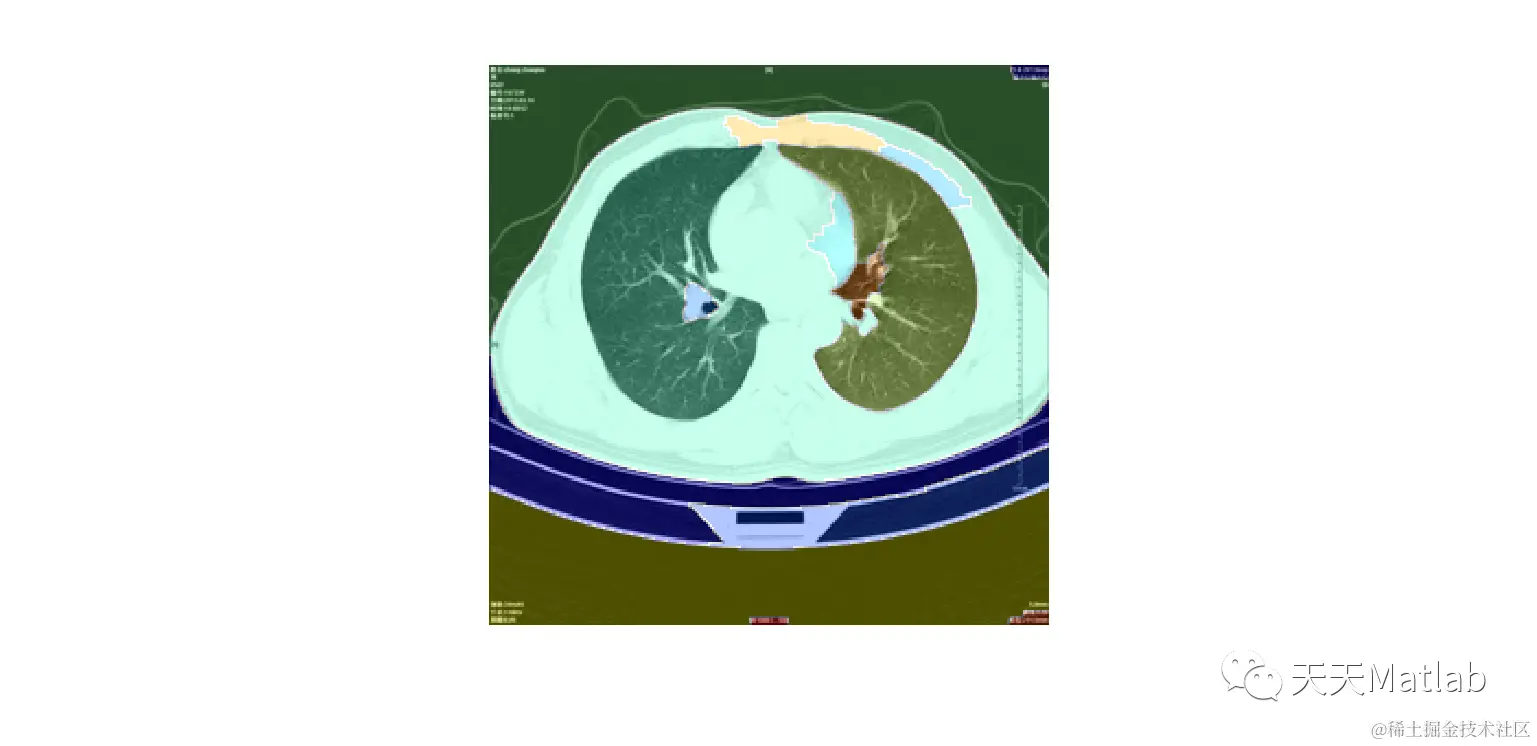

3 仿真结果